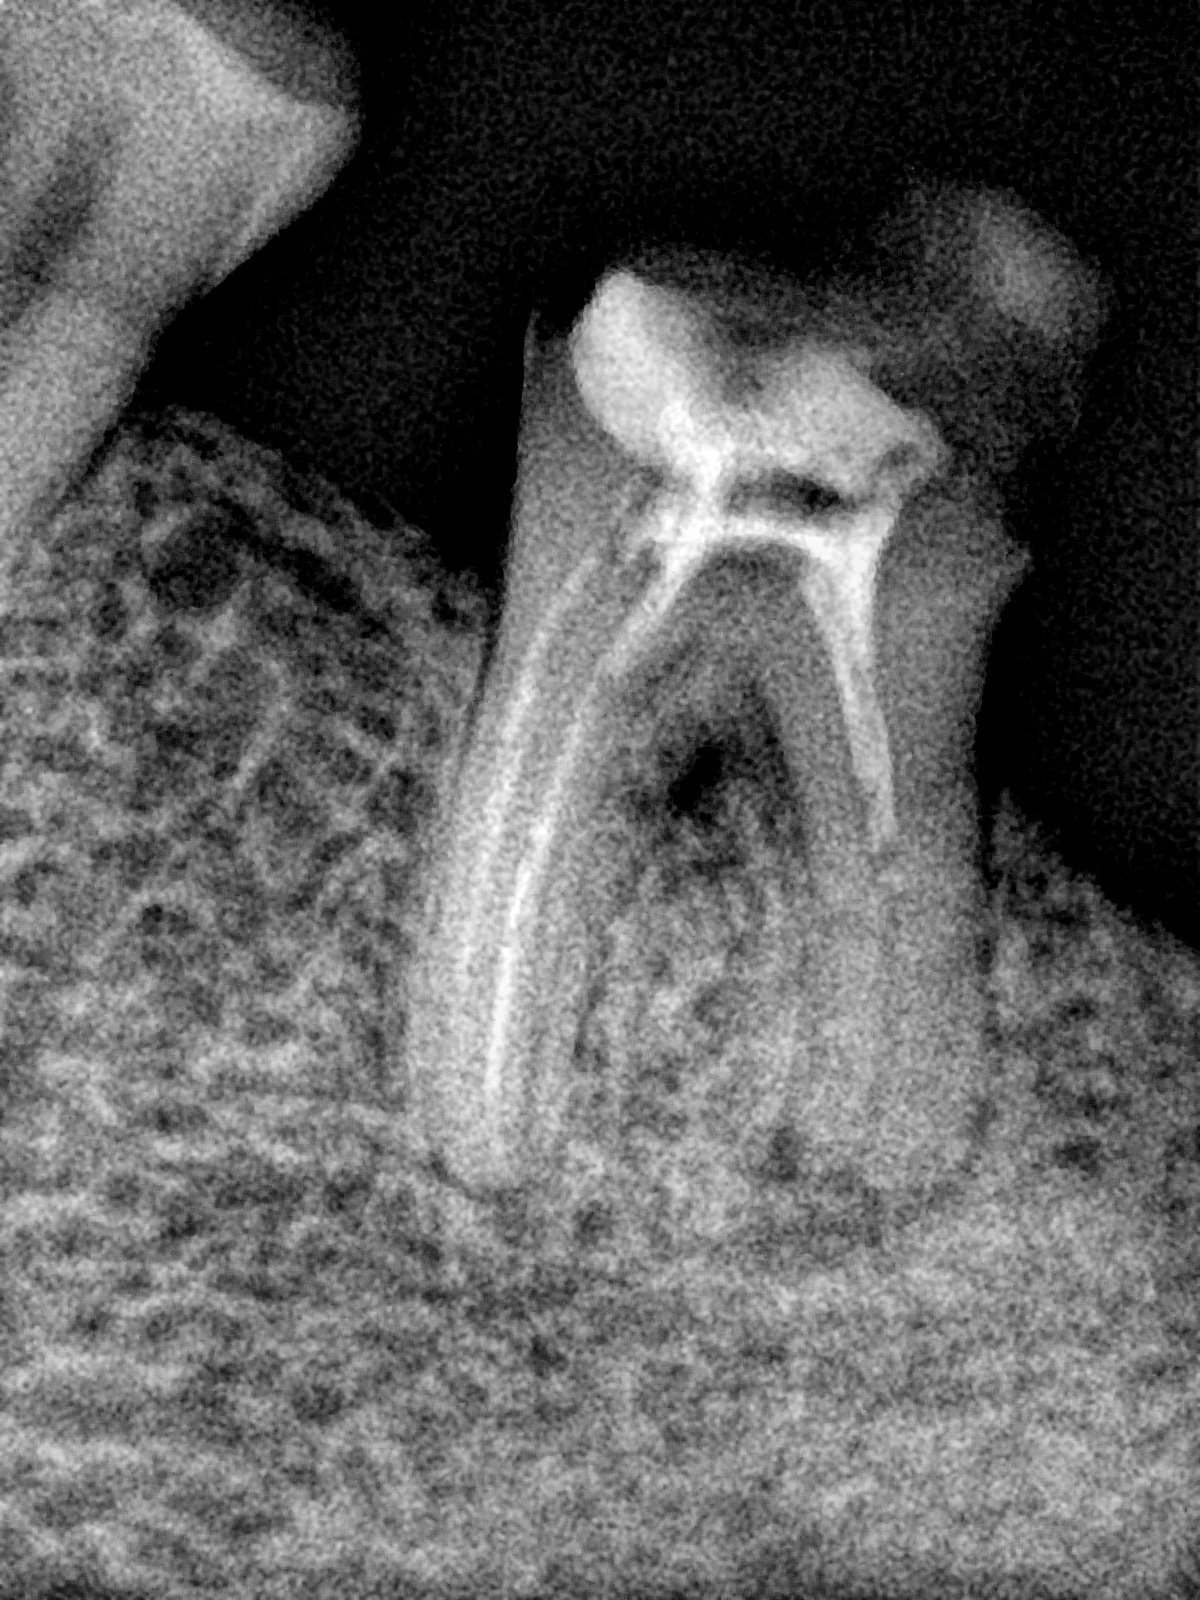

CR/DR 牙齿分割阶段记录

当前进展

- 完成了 CR/DR 牙齿相关分割训练

- 当前结果已经达到阶段预期,但仍有细节问题需要继续处理

相关测试

遇到的问题

- 训练过程中出现过 mask 下移问题

- 部分结果会出现 box 填充异常

- mask 边缘仍然有比较明显的锯齿感

参考

第二版算法问题测试